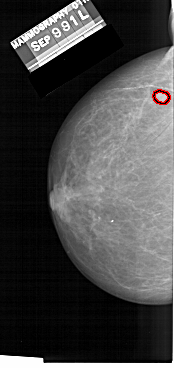

A_1481_1.LEFT_CC

LEFT_CC LINES 6256 PIXELS_PER_LINE 2956 BITS_PER_PIXEL 12 RESOLUTION 43.5 OVERLAY

FILE: A_1481_1.LEFT_CC.OVERLAY

TOTAL_ABNORMALITIES 1

ABNORMALITY 1

LESION_TYPE MASS SHAPE ROUND MARGINS CIRCUMSCRIBED

ASSESSMENT 3

SUBTLETY 4

PATHOLOGY BENIGN

TOTAL_OUTLINES 1

BOUNDARY